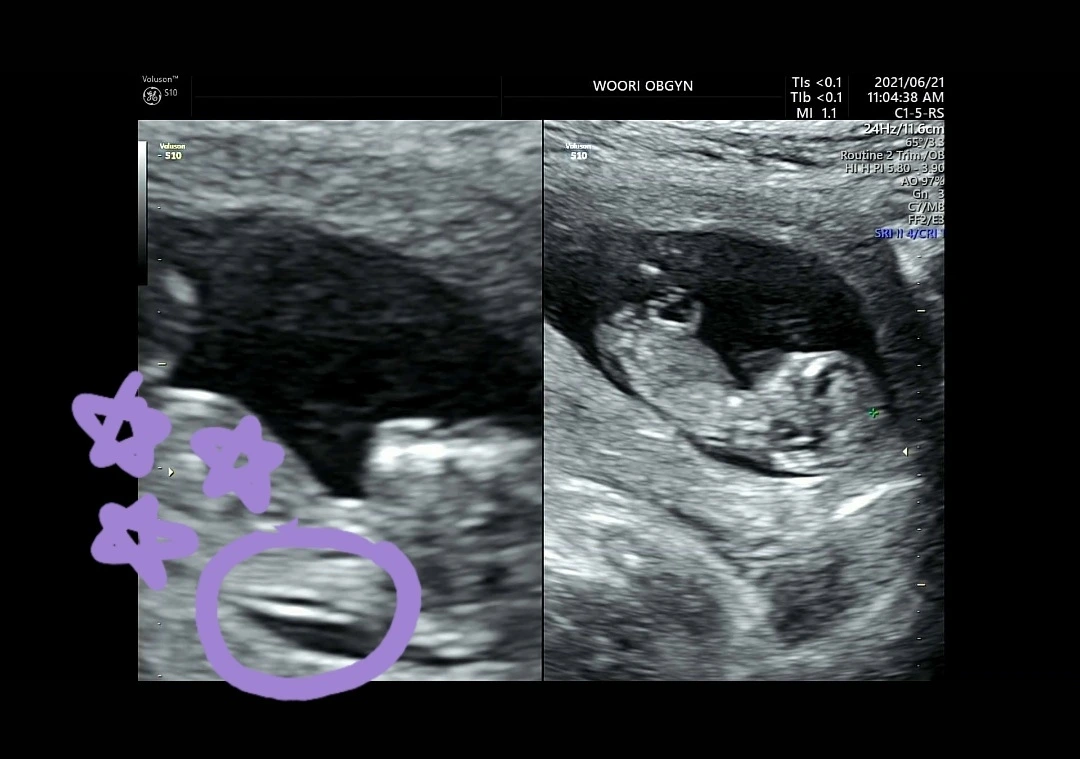

먼저 아가가 잘 크고 있는지를 확인시켜 주셨고 그다음 바로 목 투명대 길이를 재주셨다.

체크한 부분이 목투명대! 저 부분을 재서 확인 합니다!

“태아의 목덜미 뒤에 있는 이 얇은 부분은 목 투명대라고 해요. 이 목 투명대는 대부분 3.0mm를 기준으로 보고 있어요. 3.0mm가 넘으면 다운증후군 가능성이 있는데 우리 아가는 1.1mm로 보이죠~ 아주 괜찮습니다.”